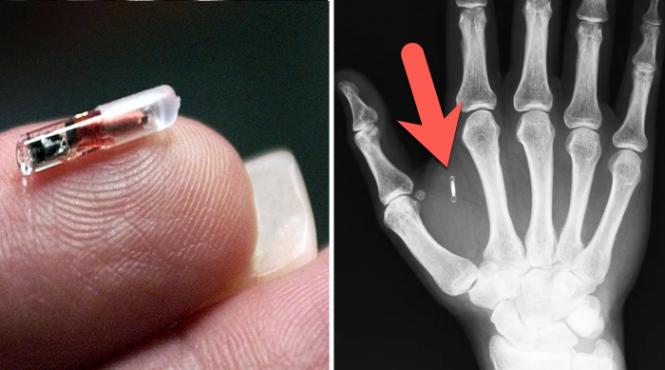

3.000 de suedezi au acceptat să se microcipeze